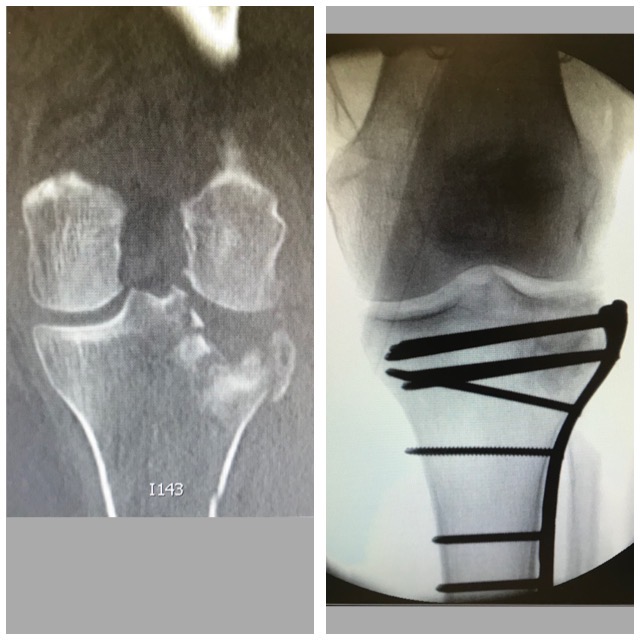

Polven

alueen murtuma

Ennen – jälkeen